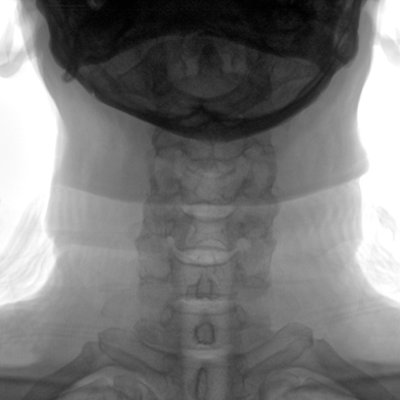

大尺寸動(dòng)態(tài)平板探測(cè)器,高DQE、低噪聲、圖像清晰。采用多分辨率圖像增強(qiáng)處理技術(shù),不同部位不同圖像處理算法,滿足客戶多樣化的需求。

采用智能變頻脈沖透視技術(shù),優(yōu)化圖像質(zhì)量的同時(shí)降低輻射劑量,呵護(hù)醫(yī)患健康